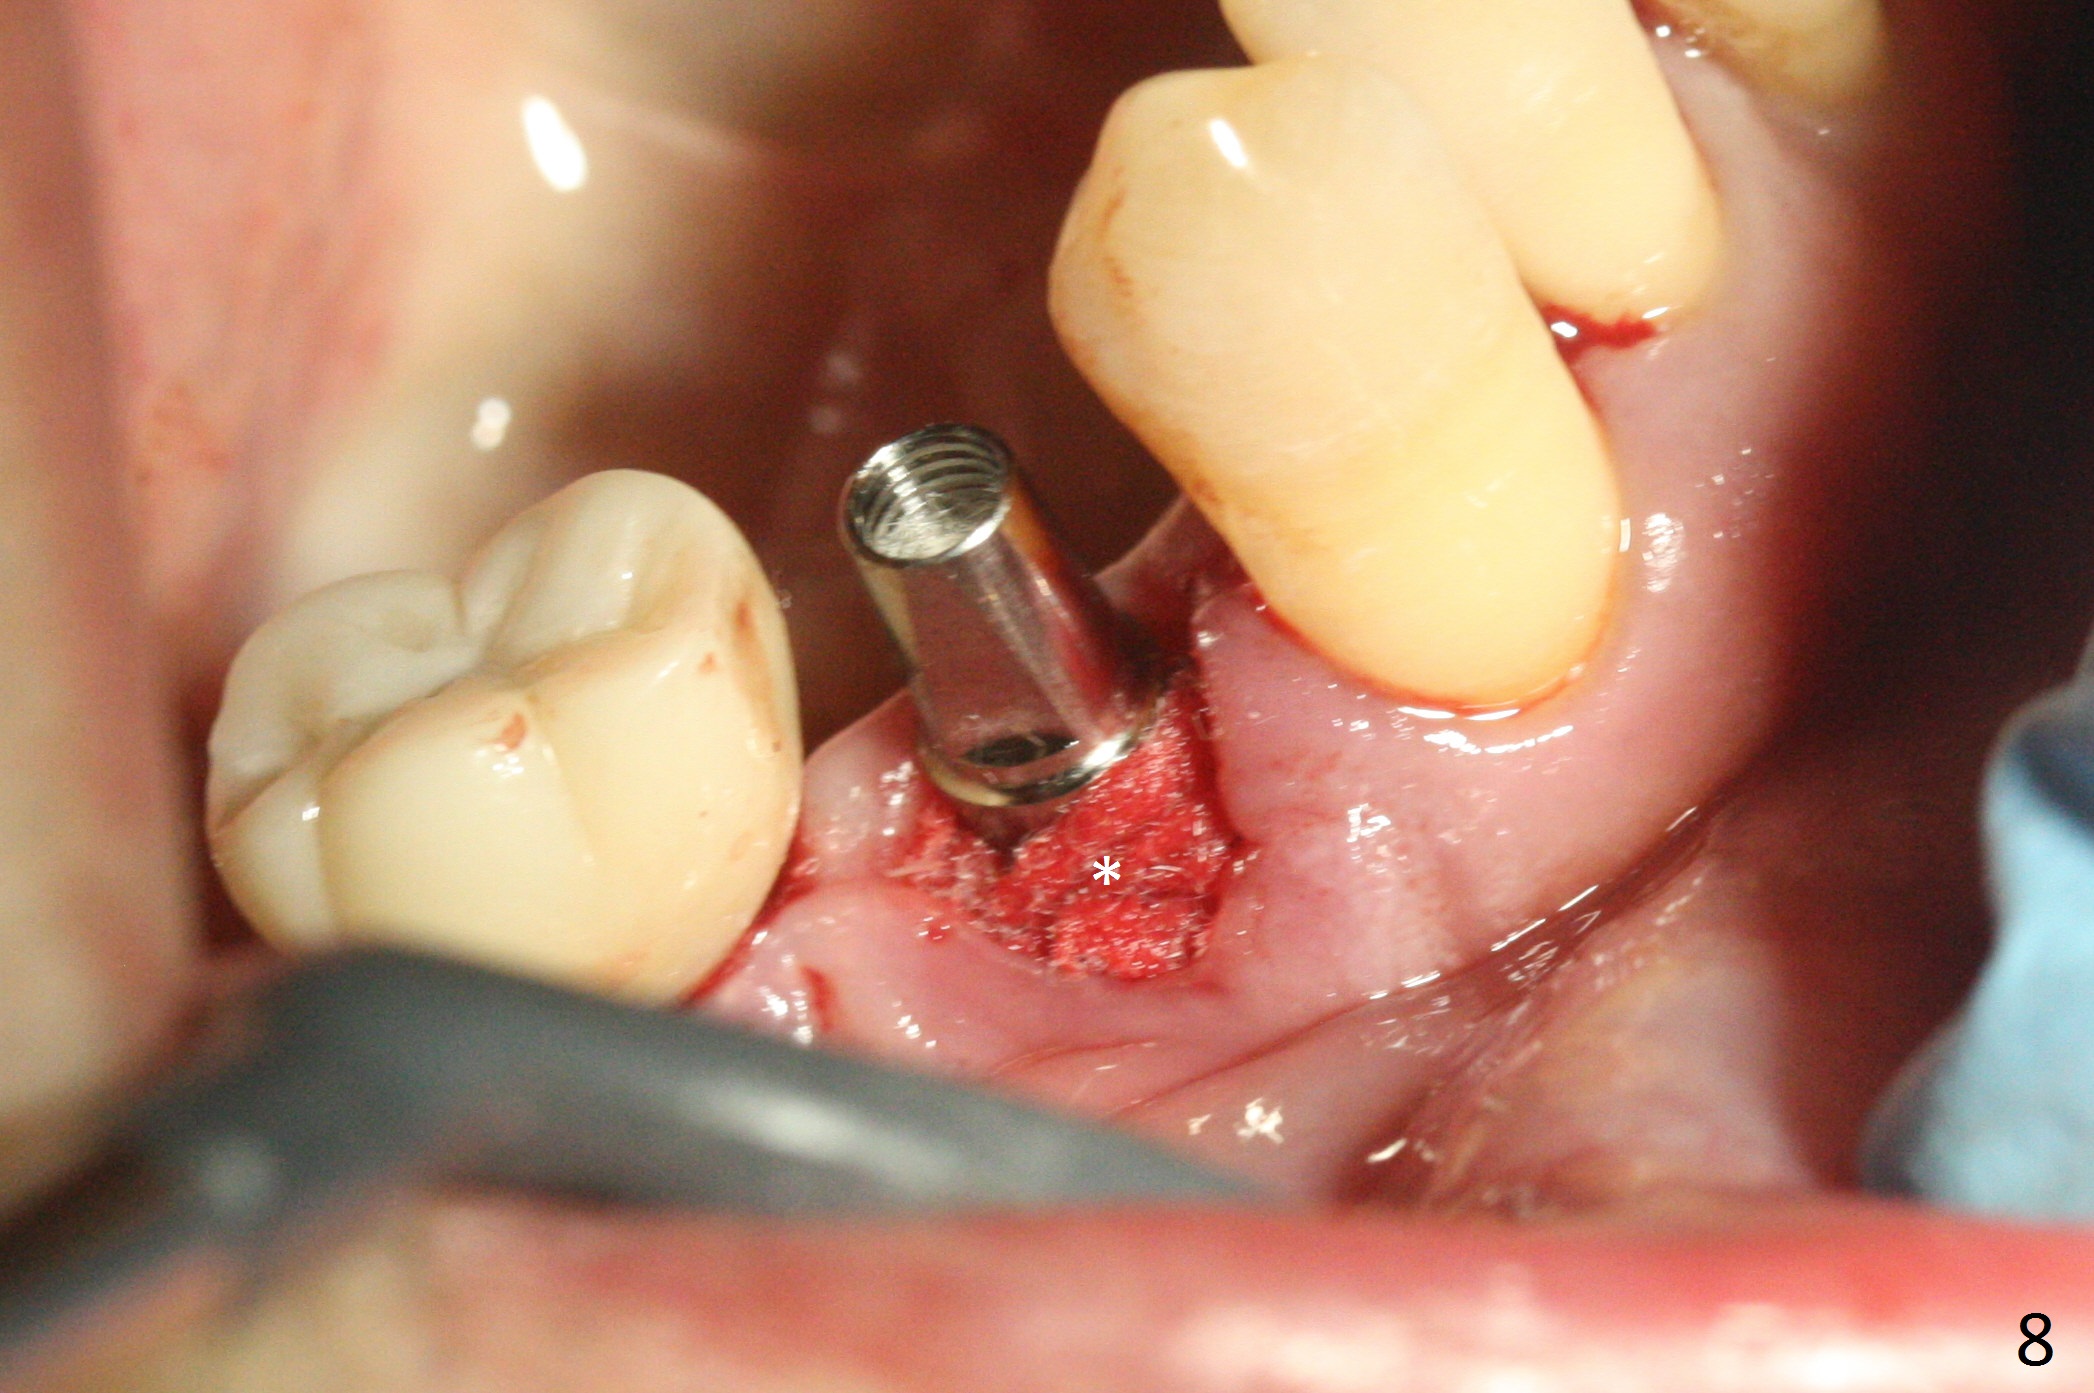

The affected tooth (#28) has buccal gingival recession (Fig.1). As expected, the buccal plate is found low after extraction. Osteotomy is established in the lingual slope of the socket with 1.5 mm drill for 13 mm (Fig.2,3). Following use of Magic Drill 3.3 mm for 13 mm, a 4x11 mm dummy implant is incompletely seated (Fig.4); it is also close to the Mental Loop (Fig.4 red line). After use of Final Drill, a 4x9 mm IBS implant is placed 4 mm and 2 mm subgingival buccal and lingual, respectively (Fig.5) with a large buccal gap (Fig.6 (40 Ncm)). After placement of allograft in the peri-implant space (Fig.7 *), a 4.5x5.7(4) mm abutment is placed (A). A piece of gauze is placed in the remaining buccal space prior to provisional fabrication (Fig.8 *). The space occupied by the gauze is later filled with collagen plug before provisional seating. The gingiva is healthy around the provisional 12 days postop (Fig.9). To reduce buccal gingival recession, the buccal margin of the provisional is shortened 4.5 months postop (Fig.10 arrow). PA taken 5.5 months postop is shown with the implant at 31. The lingual gingiva is erythematous, edematous, and recessive with +BOP and deep pockets 14 months postop (Fig.11). It appears that the small and short implant is not favorable for healing. The infected implant is removed with the missing buccal plate; bone graft is placed 15 months postop (7 months post cementation, Fig.12,13).